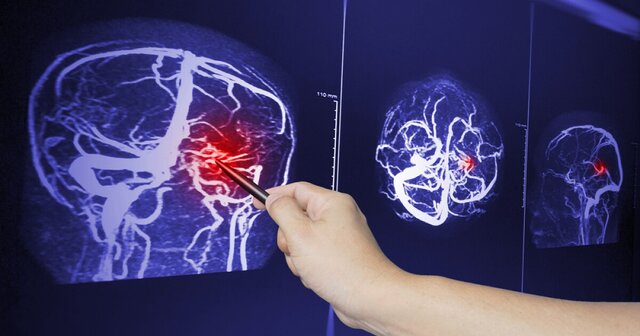

نتایج مقاله «نوروسایکولوژی دمانس (زوال عقلی)» منتشرشده در پنجمین کنفرانس ملی مطالعات آسیبشناسی روانی و روشهای نوین درمان نشان داد، نقش بیماری عروقی در علتشناسی زوال عقل در مواردی دخیل است که ارتباط مستقیمی بین رویدادهای عروق مغزی و شروع زوال عقل وجود دارد. شروع زوال عقل عروقی احتمالا ناگهانی است یا به دنبال الگوی افزایش و توقف پیشرفت بیماری رخ میدهد و مشکلات جسمی شامل بیاختیاری ادرار، تحرک کم و مشکلات تعادل است. این نوع زوال عقل بهطور معمول به این معنی است که بیماریی وجود دارد که در اختلال شناختی ناشی از بیماری عروق مغزی یا آسیب مغزی خونریزی دهنده بروز میکند.

در حالی که ارتباط بین زوال عقل و سکتههای مغزی ایسکمیک ناشی از لختههایی که خونرسانی به مغز را مسدود میکنند، بیشتر مورد توجه قرار گرفته است، تحقیق جدید که در مجله سکته مغزی منتشر شده است،  یافتههای قبلی را به خونریزیها نیز مرتبط میکند.

اما چرا خونریزی داخل جمجمهای خطر زوال عقل را افزایش میدهد؟ چند دلیل وجود دارد؛ خونریزیها ممکن است بهطور مستقیم با تحریک تجمع پروتئینی بهنام آمیلوئید بتا در مغز و رگهای خونی آن باعث زوال عقل شوند که میتواند عملکرد مغز را مختل کند. یا خونریزی و زوال عقل ممکن است بهطور غیرمستقیم با هم مرتبط باشند زیرا همان عوامل مانند آسیب مزمن به عروق خونی در مغز، خطر ابتلا به هر دو بیماری را افزایش میدهد.